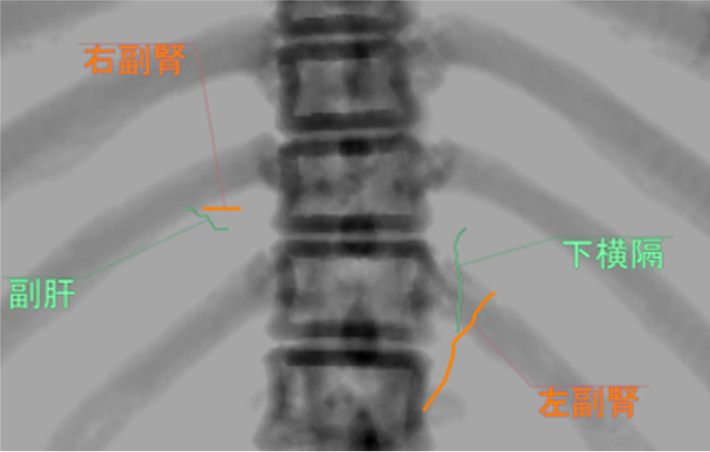

当該疾患の診断における造影CTの役割

原発性アルドステロン症は, 治癒可能な二次性高血圧であり, 本態性高血圧より脳・心血管, 腎合併症の頻度が高く, その診断および治療の重要性が指摘されている, 片側性のアルドステロン症の場合, 外科的切除によりアルドステロン過剰の正常化, 高血圧および臓器障害の改善・防止が期待できる, このため, 手術が考慮される場合には副腎静脈サンプリングによる機能的局在診断を行う, 原発性アルドステロン症診療ガイドライン20211)では, この副腎静脈サンプリングの成功率を向上させる方法の一つとして, ダイナミックmulti-detector row CT(MDCT)が推奨されている, MDCTでは, 横断像やMPR(Multi planar Reconstruction)を用いて, 副腎静脈の走行やvariationの確認などを行うが, これに加え当院では,仮想透視画像を作成し, 右副腎静脈の下大静脈開口部のレベルや, 副肝静脈との位置関係など, 立体的な解剖学的把握を行っている, その結果, サンプリング時に, スムーズかつ的確なカテーテル操作が可能となる.

注意点としては, CTでは深吸気時に撮影されるのが一般的であるが, カテーテル操作は, 安静呼吸下で施行されるため, 副腎静脈の位置がやや異なることがある. 当院では, 呼吸性変動を踏まえて, 後期動脈相, 門脈優位相を呼気にて撮影し, 平衡相のみ吸気にて撮影している.

副腎静脈サンプリングにおけるIVR支援画像としての位置付けとなるため, CT検査においての安定した呼気停止の検査説明が重要となる. 当院では位置決め撮像(Topogram), 単純, 後期動脈相, 門脈優位相を呼気停止にて撮影, 平衡相のみ副腎の呼吸性移動を観察する目的で吸気撮影を行っている. 被検者への説明を丁寧に行い理解を得ることを心がけている.

本検査における後期動脈相は, 右副腎静脈と下大静脈との合流部, また左副腎静脈と下横隔静脈, 腎静脈との合流部の形態評価が求められる重要な撮影時相である. そのため30sec注入時間固定法とbolus tracking法の併用を行い, 腹部下行大動脈において+100HUのCT値上昇をトリガーとし, 20secのdelay timeにて後期動脈相の撮影を行っている. その後の門脈優位相は, トリガーから40secの撮影とし, 主に副肝静脈と下大静脈との合流部の形態評価が目的とされる. 造影コントラスト向上のため. 可能な限り低管電圧撮影が行えるよう留意している. なお, 本症例は, 造影剤量がプロトコルより少ない症例であったが, 低管電圧撮影や後期動脈相の最適な撮影タイミングにより, 副腎静脈を良好に描出し得た.